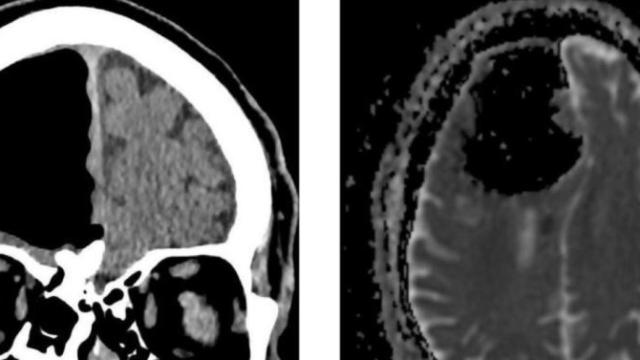

Radiodiagnóstico o radiología